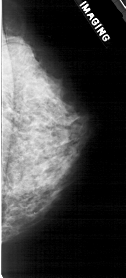

A_1926_1.LEFT_CC

LEFT_CC LINES 4966 PIXELS_PER_LINE 2296 BITS_PER_PIXEL 12 RESOLUTION 43.5 OVERLAY

FILE: A_1926_1.LEFT_CC.OVERLAY

TOTAL_ABNORMALITIES 1

ABNORMALITY 1

LESION_TYPE CALCIFICATION TYPE PLEOMORPHIC DISTRIBUTION CLUSTERED

ASSESSMENT 4

SUBTLETY 2

PATHOLOGY BENIGN

TOTAL_OUTLINES 1

BOUNDARY